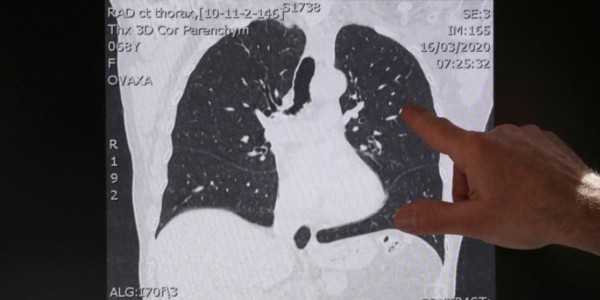

“En algunos momentos tempranos de la epidemia había videos diciendo que (había) fibrosis pulmonar por coronavirus. El patrón que vemos en fibrosis pulmonar idiopática es completamente diferente al que vemos en los pacientes con coronavirus.